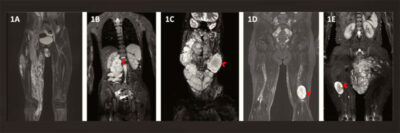

Neuromas plexiformes mostrados em ressonância nuclear magnética – Foto: pmc.ncbi.nlm.nih.gov – Srivandana Akshintala e colaboradores, Neuroncology, 2020.

Metade das pessoas com NF1 desenvolve neurofibromas plexiformes ao longo da vida. Em muitos casos os tumores são inoperáveis por crescerem em áreas delicadas, próximas a nervos, vasos sanguíneos ou órgãos vitais. Embora sejam benignos, eles podem evoluir para formas malignas mais agressivas, como os tumores malignos da bainha do nervo periférico (MPNST).